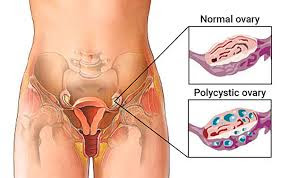

Οι πολυκυστικές ωοθήκες περιέχουν πολλές μικρές κύστες, οι οποίες συνήθως δεν ξεπερνούν τα 8 χιλιοστά σε μέγεθος και εντοπίζονται τις πιο πολλές φορές ακριβώς κάτω από την επιφάνεια της ωοθήκης.

Οι μικρές αυτές κύστεις είναι ωοθυλάκια που περιέχουν ωάρια, λόγω όμως ορμονικών διαταραχών, τα ωοθυλάκια αυτά δεν έχουν αναπτυχθεί πλήρως και παρουσιάζουν στασιμότητα στη πορεία εξέλιξης τους. Οι πολυκυστικές ωοθήκες είναι συχνές στις γυναίκες και απαντώνται περίπου στο 20 – 30% των γυναικών.

Κατά τη γυναικολογική εξέταση, οι ωοθήκες τις περισσότερες φορές έχουν αυξημένο μέγεθος λόγω των πολλών μικρών κυστών που βρίσκονται μέσα σε αυτές. Αυτό μπορούμε να το διαπιστώσουμε ευκολότερα με τον υπέρηχο που γίνεται και την μέτρηση όγκου ωοθηκών.

Κατά το υπερηχογράφημα σύνηθες εύρημα είναι οι πολυάριθμες μικρές κύστες περιφερειακά στην ωοθήκη. Επίσης βρίσκουμε συνήθως ένα παχύ ενδομήτριο (εσωτερική επένδυση της μήτρας) λόγω της άστατης εμμηνορρυσίας.